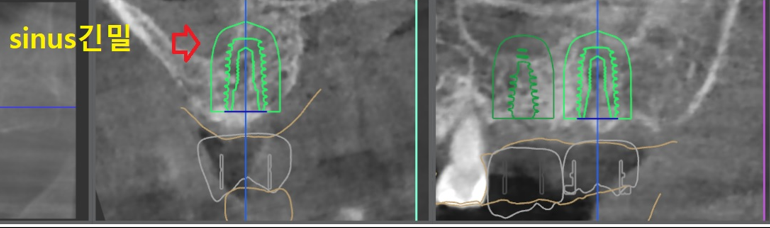

『전치부, 디지털 진단』

먼저, 앞니 임플란트 를 심을 위치 및 기울기를

결정해야 됩니다. 사진에서 보실 수 있는것은

- Narrow kit 사용

- 치조골의 단면

을 확인을 할 수 있는데 Narrow kit 를

사용한다는 뜻은 mini size implant fixture 를

사용한다는 말과 같습니다.

즉, 이 곳에는 직경 3.3파이, 10mm 크기의

고정체를 심기로 결정내렸으며

한 가지 더 주의해야 될 점은, 비구개신경과

거리가 다소 가까웠기 때문에 이렇게

디지털 진단을 내리더라도 실제 시술에 있어서는

해부학적 구조물들의 위치를 인지를 하고 진행을

해야 더 좋은 결과를 얻을 수 있습니다.

즉, 디지털에 너무 의존을 하지 않는다는거죠.

『구치부, 디지털 진단』

이제 구치부쪽인, 어금니 쪽을 진단 내립니다.

여기 또한 똑같이, 위치 및 기울기를 결정 한 뒤에

뼈의 단면 및 해부학적 구조물들의 위치를

가늠해보는데, 여기에는 상악동과 거리가

가까워서 상악동거상술을 해야 된다는 결론을

내리게 되었었습니다.

전치부 쪽도, 구치부쪽도 어느 하나